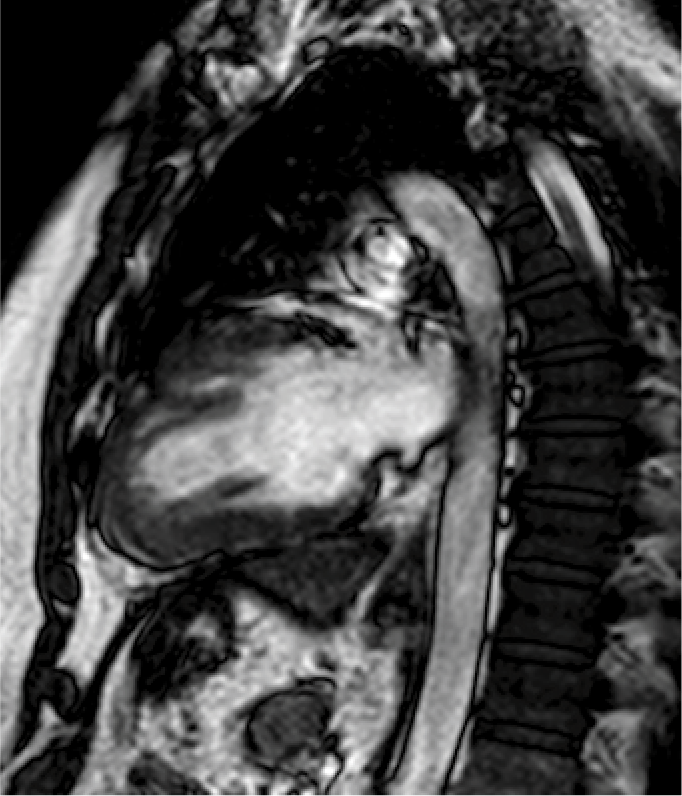

Resonancia magnética cardiaca

La resonancia magnética cardiaca es un una técnica de imagen que permite estudiar detalladamente y en una sola exploración la función y la estructura del corazón. Este auxiliar diagnóstico utiliza un potente campo magnético, sin radiación, para generar imágenes detalladas de las estructuras del corazón.

La resonancia magnética esta indicada en la evaluación de las cardiopatías congénitas tanto en el niño como en el adulto, en la evaluación de la perfusión miocárdica (resonancia cardiaca con gadolinio), de la función cardiaca, de las enfermedades del músculo cardiaco (miocardiopatías), tumores del corazón y del tejido que rodea al corazón (pericardio).

Este estudio es bien tolerado por la mayoría de las personas. El campo magnético no es dañino, pero puede causar el mal funcionamiento de algunos dispositivos médicos. La mayoría de los implantes ortopédicos no presentan riesgos, pero siempre debes informar al técnico de resonancia magnética si tiene algún dispositivo o metal en su cuerpo.